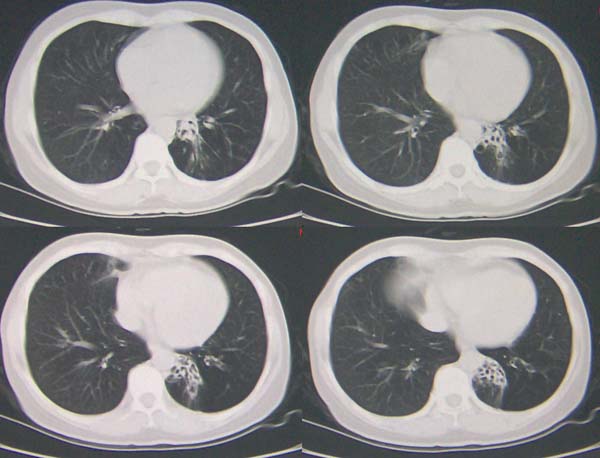

标题: CT9509:女,50岁,咳嗽,发热,38度, [打印本页]

标题: CT9509:女,50岁,咳嗽,发热,38度,

左肺下叶支气管呈囊状扩张。考虑支扩。

左下肺支气管扩张;支气管炎;左下肺纤维条索并局部胸膜肥厚。

左肺下叶支气管呈囊状扩张。考虑支扩。胸膜肥厚\\粘连,建议增强除外肺隔离症.

左肺下叶支气管呈囊状扩张。考虑支扩伴感染

左肺上叶小片状病灶密度底,左下叶见多发小囊状病灶,周围透光增强无纹理,沿左侧膈肌旁见条带状病灶边界清晰,

1左肺上叶炎症,左下支气管扩张伴感染,肺隔离征待除外,2肺大泡,3左下叶内基底段不张?

左肺舌叶及右肺下叶背段斑片状低密度影,左肺下叶内基底段网格状阴影,周围肺野透亮度增高,结合临床咳嗽、发热,38度,无咯血及反复感染病史,考虑双肺炎症,左下肺发育不良。建议抗炎治疗后复查或增强与左下肺隔离症鉴别。